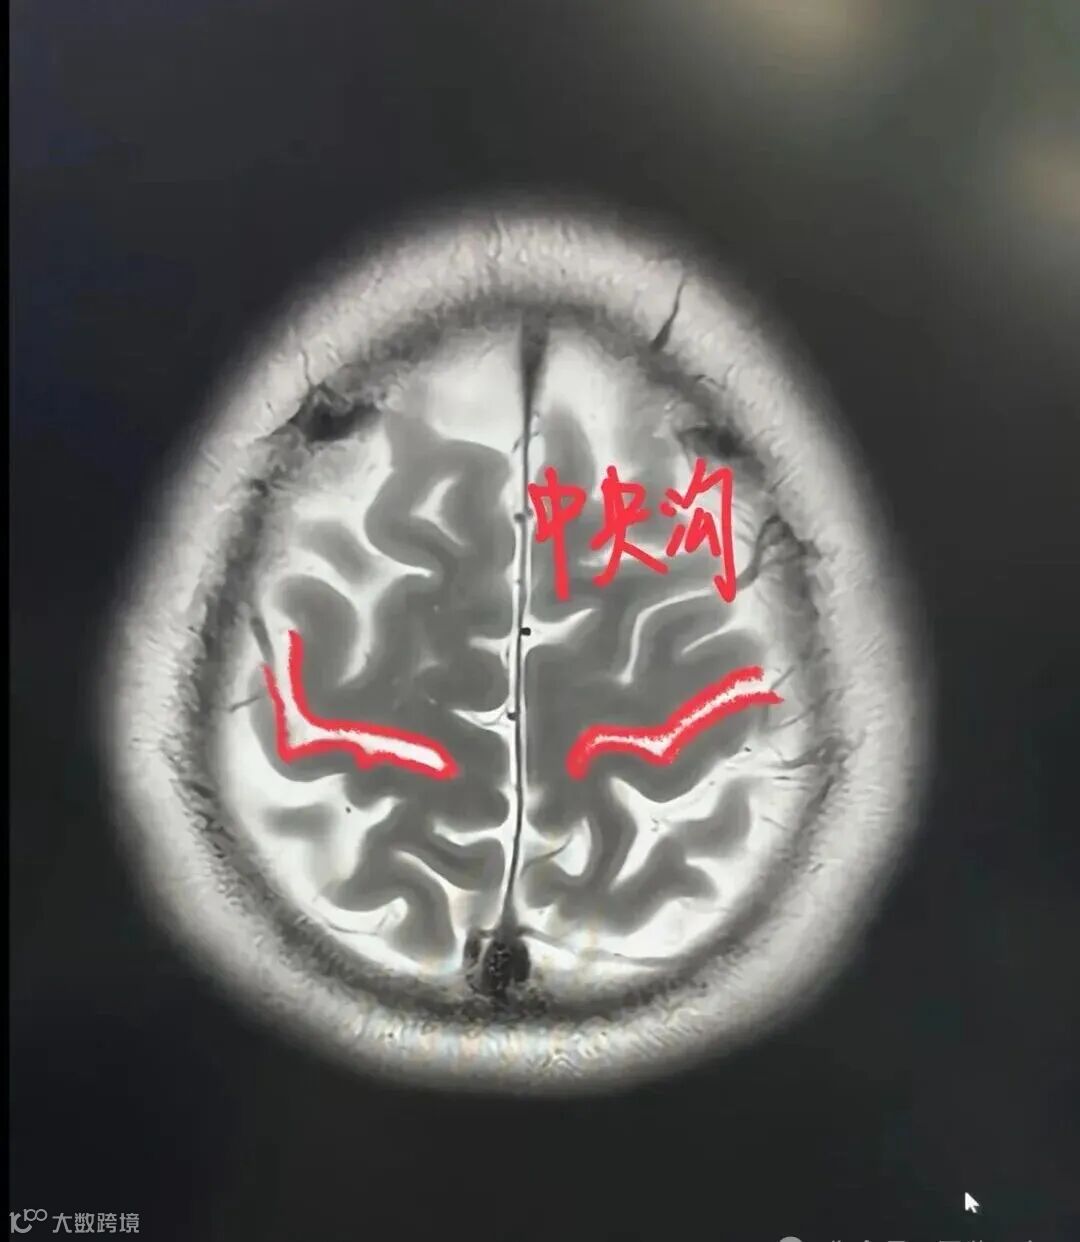

中央沟:从冠状平面将大脑分成额叶和顶叶的脑沟。